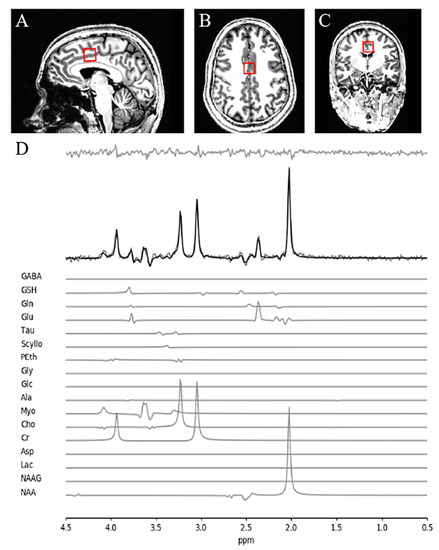

2.2. Magnetic Resonance Spectroscopy (MRS) Acquisition and Analysis